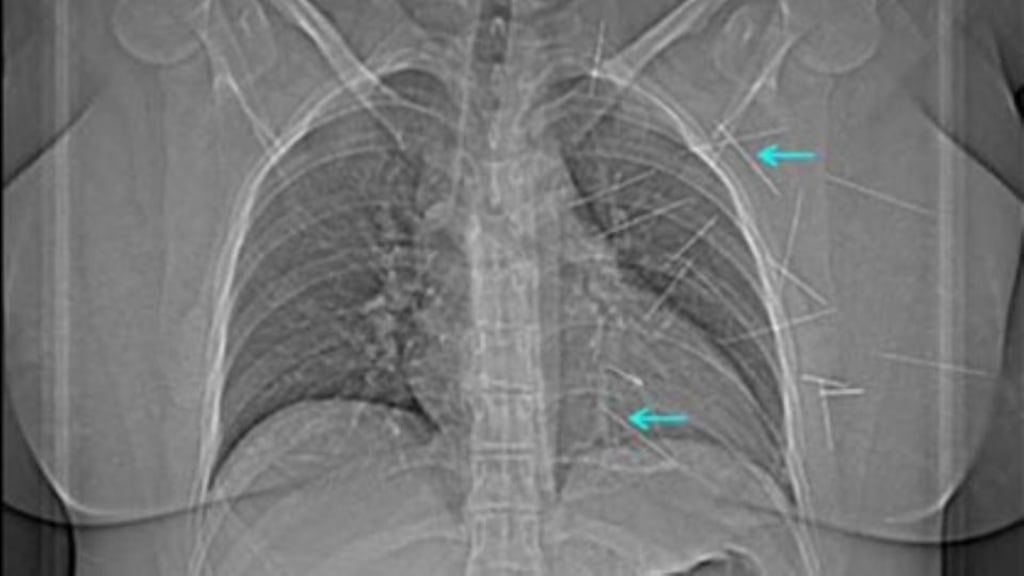

The patient attended the emergency department reporting that she had a single needle lodged in her chest, but a subsequent X-ray detected at least 19 foreign objects in her body.

A needle that was penetrating the right ventricle of the patient’s heart was removed, along with two needles that had been lodged in her abdomen. The operation was completed without complication.

“Even though a foreign body is only partially inserted into the heart, it can become completely embedded in the wall due to strong cardiac contractions.”

The movement of such objects into the chambers of the heart can be fatal, according to the report.